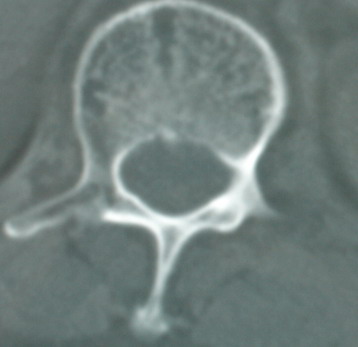

以下是引用卜一在2008-6-3 19:33:00的发言:[br]双肺结节,以双上肺分布为多,期间搀杂片状致密影及索条致密影。考虑:继发性肺结核伴血型播散可能性大。不除外肺泡ca的可能!另:椎体退变!

以下是引用panyishengct在2008-6-3 21:09:00的发言:[br]双上肺弥漫性小结节影,纵隔窗内钙化淋巴结影,考虑矽肺或/和tb可能性较大,不除外肺ca可能。腰椎考虑退变。 [br][br]